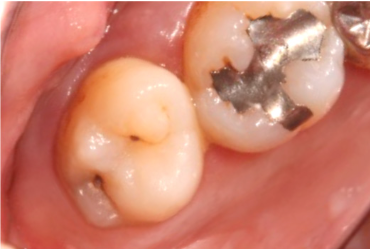

セラミック治療(自費)

• 治療前

• 治療後

保険適用外の「セラミック治療」も行っています。「レジン充填法」よりも審美性が高く、衛生的で長持ちします。